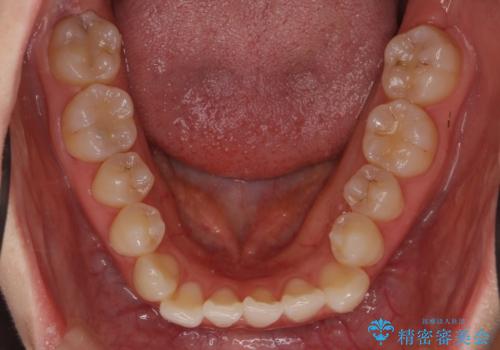

- 前歯の並びを主訴に来院。

マウスピースで歯を抜かずに治療しています。

左上の前歯が飛び出しており、唇が笑った時に引っかかっていたのが解消しています。

左上の前歯は小さいため、(矮小歯)左右対称になるようにセラミックで形を修正する治療も併用しています。

歯を大きくかぶせるスペースを作るため、右上の奥歯を後ろに下げています。

左にずれていた上の正中も揃い、大変喜んでいただきました。